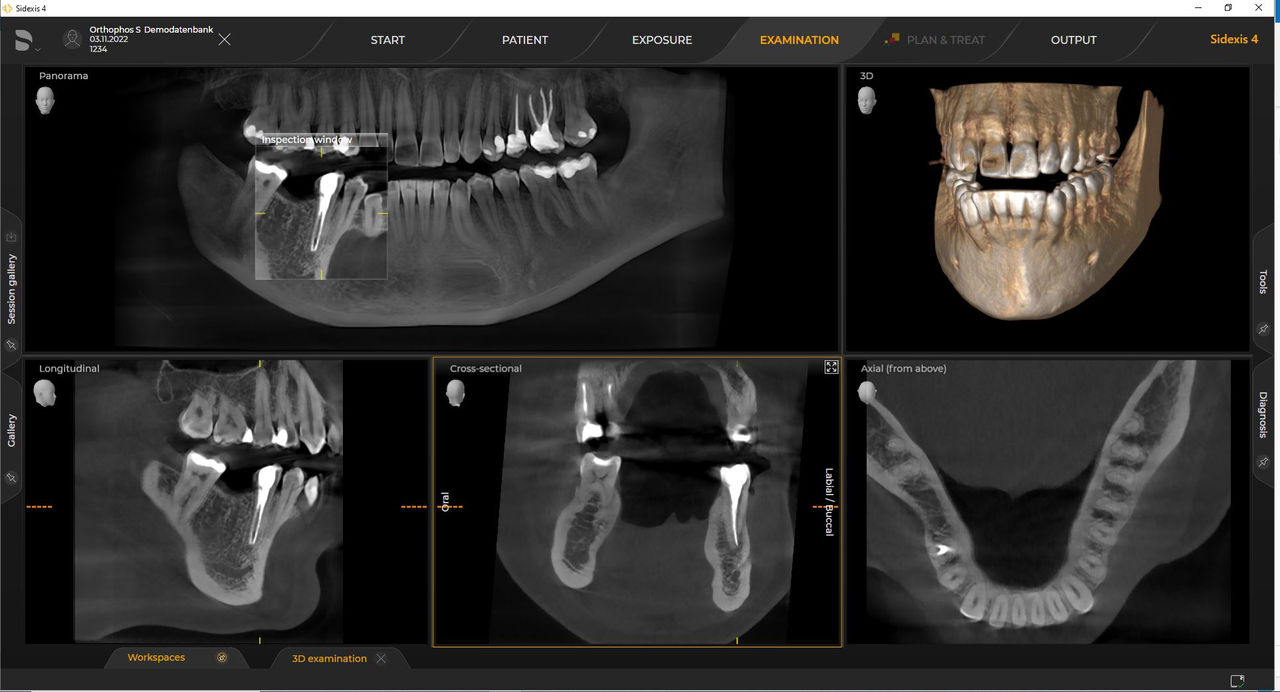

Con el modo de dosis baja inteligente 3D, obtiene imágenes 3D en el rango de dosis de una imagen radiológica 2D. En el modo HD (hasta 1400), las imágenes individuales se obtienen durante una única rotación y se convierten en un volumen 3D con hasta 80 μm para imágenes de bajo ruido en alta resolución.

Las unidades de radiología de Dentsply Sirona funcionan exclusivamente con Sidexis 4. Sin embargo, la migración de datos de Sidexis XG a Sidexis 4 es muy fácil. Sidexis 4 permite una experiencia digital completa con las últimas herramientas